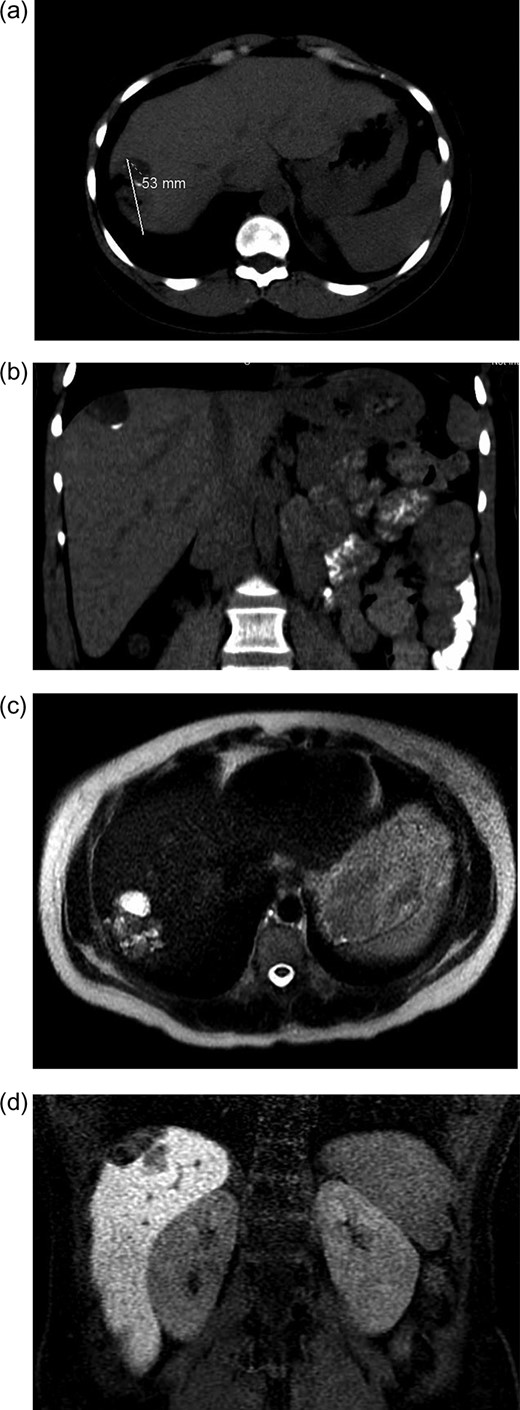

Initial radiographic evaluation with computed tomography (CT) demonstrated a mass in the dome of the liver (Fig. 1a and b). A multiphase magnetic resonance (MR) scan of the abdomen followed and a 3.7 × 5 × 2 cm3 complex lesion was found, containing: cystic elements, macroscopic fat and a calcification (Fig. 1c and d). Percutaneous CT-guided biopsy was then performed and pathology showed atypical columnar epithelium with neuroendocrine differentiation. Both an upper and lower endoscopy did not identify any primary tumor. A positron emission tomography scan did not show evidence of metastatic disease or evidence of other pathology.

(a and b) CT abdomen and pelvis without IV contrast demonstrating tumor in axial (a) and coronal views (b). (c and b). MR abdomen and pelvis with and without IV contrast (Eovist, gadoxetate disodium, Bayer Pharmaceuticals) showing 3.7 × 5 × 2 cm3 complex lesion containing cystic elements, macroscopic fat and calcification in axial (c) and coronal (d) views.